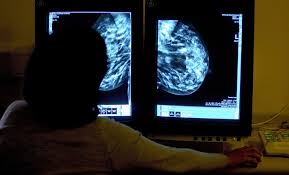

ইংল্যান্ডের হাজার হাজার মানুষ স্টেজ ফোর ক্যান্সারে আক্রান্ত

ইংল্যান্ডের হাজার হাজার মানুষ স্টেজ ফোর বা শেষ ধাপের ক্যান্সারে আক্রান্ত বলে জানিয়েছে ’ম্যাকমিলান ক্যান্সার সার্পোট’র এক নতুন গবেষণায়।

এমা ইউং এর বয়স ৩৯ বছর। যখন তাঁর বয়স ৩৫ তখন স্তন এবং হাড়ের ক্যান্সার ধরা পড়ে।

২০১৪ সালে ডাক্তার তাঁর ভুল পরীক্ষা করে। এতে করে ক্যান্সার আরো কিছুটা ছড়িয়ে পড়ার সময় পায়। পরে জানা যায় তিনি স্তন এবং হাড়ের ক্যান্সারের আক্রান্ত।